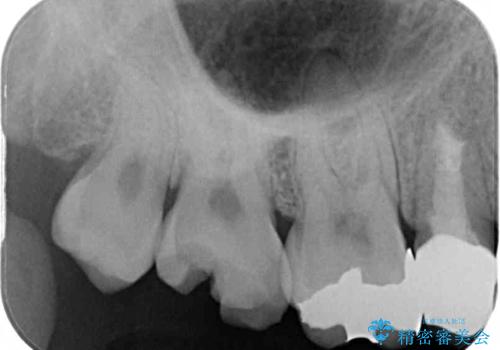

- 上の奥歯に装着されていた銀歯が外れてしまったとのことで来院された患者様です。

強い咬合力により銀歯と歯の間に隙間ができ、その隙間から虫歯となって外れてしまったと想像されました。

銀歯では歯と充填物の固さに違いがあり、再度外れてしまうリスクが高いため、固さが歯と近いゴールドインレー(PGAインレー)にて修復することとしました。